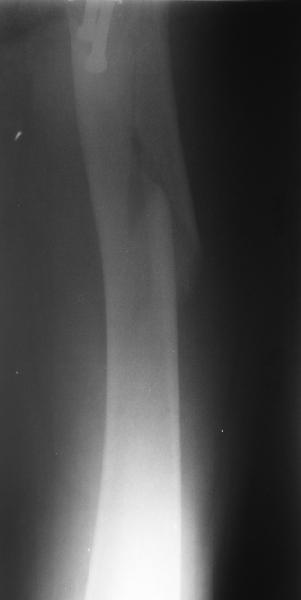

1LateralAnother lateral

Женшина 69 лет оперирована у нас 2 года назад по поводу перелома шейки. Ходила дома без дополнительной опоры, на улице - с тростью.Сегодня утром села мимо табуретки. Поскольку наша бывшая пациентка, сегодня же из области родственники привезли к нам. Картинка в приложении. Какие будут предложения по тактике?

Regarding this specific patient, it is quite difficult for me to discern the exact fracture pattern and therefore treatment suggestions. It appears to be a spiral fracture starting just proximal to the less trochanter and extending distally 6 or more cm into the shaft with medial displacement of the distal fragment. The lesser troch is a seperate fragment. The 2 year old femoral neck fracture appears to have healed in good position I really can't tell where the fracture starts laterally, but presumably it's near the distal most screw.

I can't tell if there is further comminution of the shaft or the greater trochanter. I can barely see the fracture on the lateral radiograph. I'm not sure but I don't see AVN of the femoral head nor OA of the hip. Her overall bone quality appears normal for a 68 year old. I don't see any loosening of the screws but I can't tell for sure.

The fracture extention well into the shaft makes intramedullary fixation somewhat more appealing than plate fixation and contrasts with the case posted by Bill. A reconstruction nail with proximal locking into the femoral head and neck after screw removal and reduction would be reasonable.

Еще одна боковая проекция. На сегодня назначен закрытый интрамедуллярный остеосинтез. Реконструкционного гвоздя для этой больной не нашлось, придется делать обычным.

Another lateral view. A closed nailing is scheduled for today. No reconstuction nail is available so a usual one is planned.